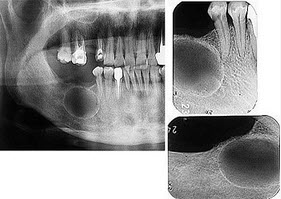

170、单项选择题

发现下前牙变色,唇侧牙龈一肿物一月余,经X线检查,结果如图

。最可能的诊断是()